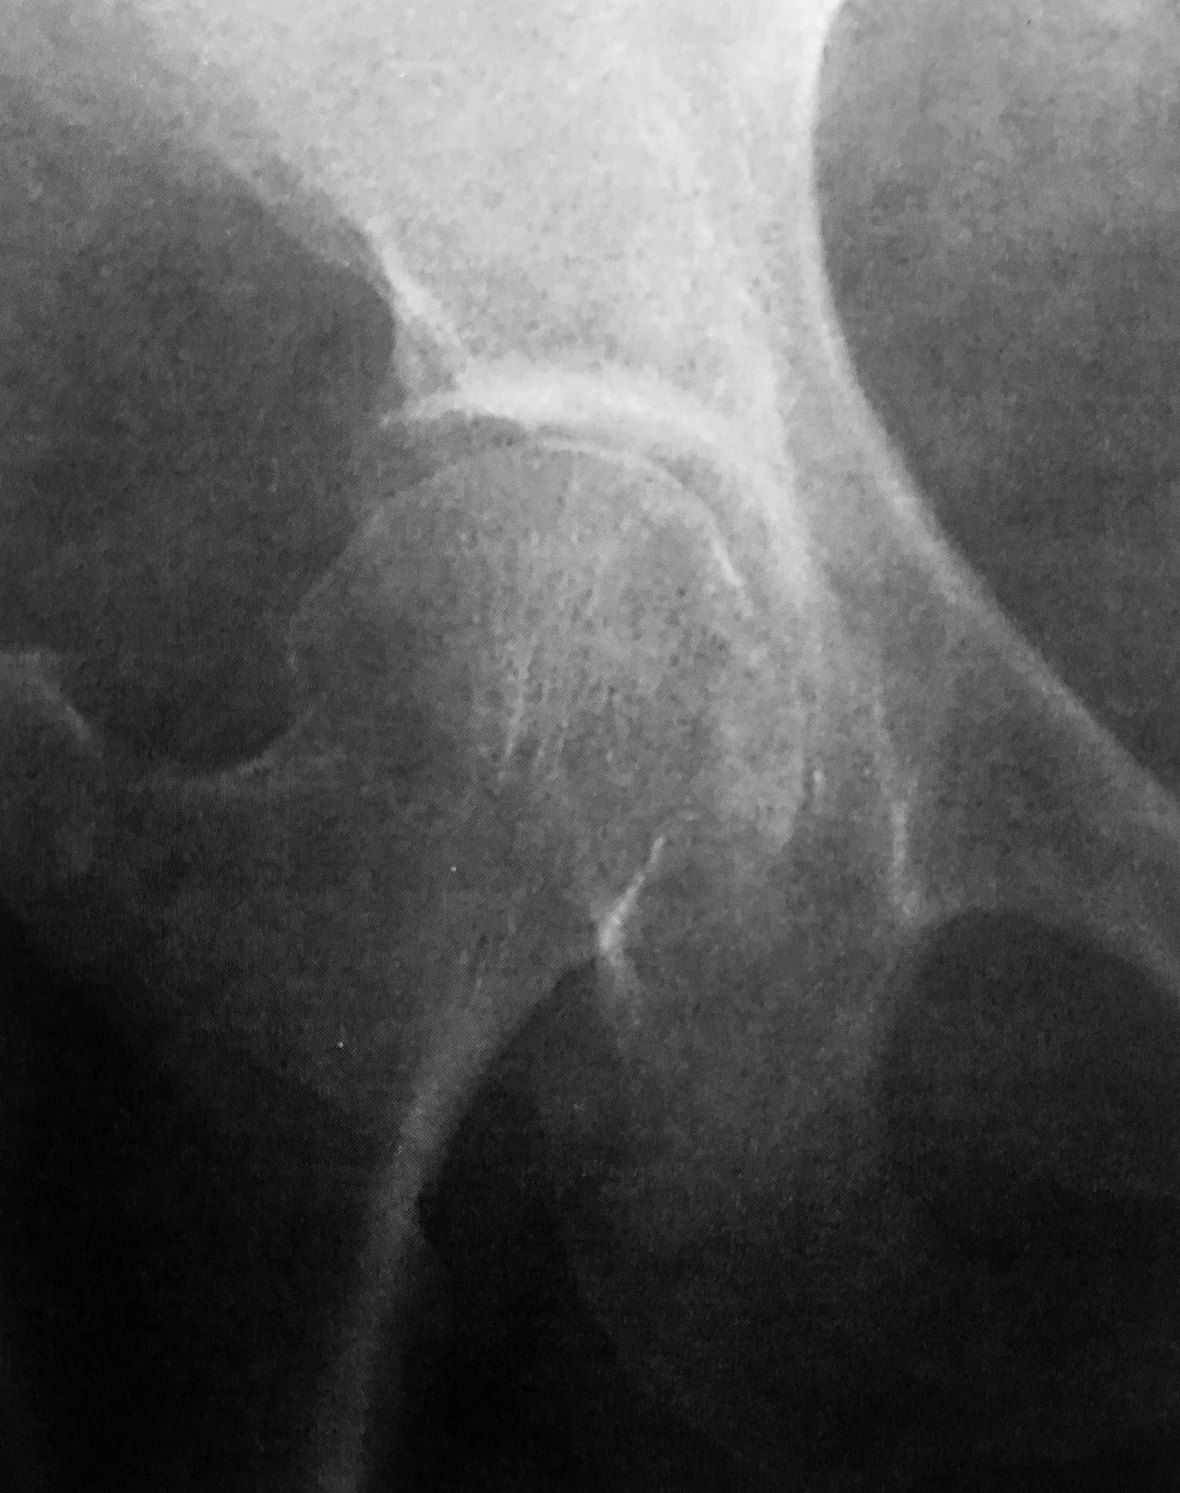

新 月 征

髋关节 X 线平片示右侧股骨头关节面下新月形透亮影,提示新月征

判读要点:

1、新月征是 III 期股骨头坏死的直接征象;

2、新月征对诊断股骨头坏死具有特异性,提示股骨头早期塌陷;3、在 X 线骨盆或髋关节正位片显示。